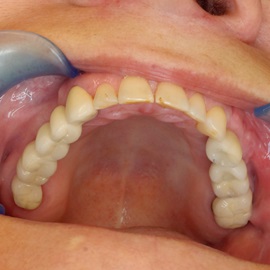

Odbudowa lewego dolnego trzonowca.

Odbudowa prawego dolnego trzonowca.

Uzupełnienie trzonowców: szóstki i siódemki na implantach.

Odbudowa kości, dziąsła, implantacja, korony protetyczne, dwa prawe dolne trzonowce.